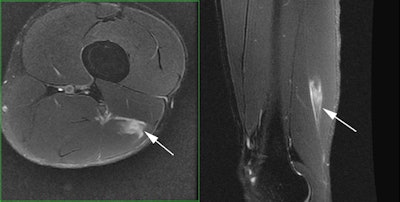

Professional tennis player with acute onset right groin pain during a match. Axial and coronal fat-saturated T2-weighted MR images demonstrate an acute injury of the right obturator externus muscle with a small focal hematoma. All images courtesy of Dr. Ara Kassarjian.